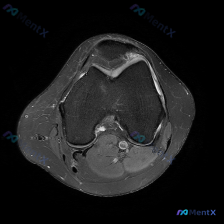

看到一份很有讨论价值的膝关节MRI病例,整理了影像发现和分析思路,和大家一起交流。 病例影像基本信息 这是一份膝盖MRI的轴位T2加权图像,扫描层面位于髌股关节滑车沟层面,可观察到以下明确异常: 1. 髌骨改变:髌骨后方关节软骨信号不均匀、局部T2高信号,软骨形态不规则、厚度变薄;髌骨边缘骨质可见高...

看到一份膝关节轴位MRI的读片资料,软骨异常是核心发现,整理了影像特征和完整分析思路,和大家分享讨论。 一、影像基本信息 这是膝关节髌股关节层面的脂肪抑制序列MRI(PD-FS或T2-FS),图像特征: 1. 髌骨、股骨皮质低信号,骨髓脂肪信号正常 2. 核心异常:髌骨后方关节软骨信号不均匀,局部高...

看到这个膝关节MRI的病例,整理了完整的影像表现和分析思路,分享给大家一起讨论。 一、病例基本影像信息 这是一份膝盖MRI T2序列轴位图像,扫描层面位于髌股关节层面,可见髌骨与股骨滑车关节面,评估结果如下: 1. 关节软骨:髌骨后方关节软骨为低信号带,髌股关节外侧面可见不均匀高信号改变,提示软骨磨...